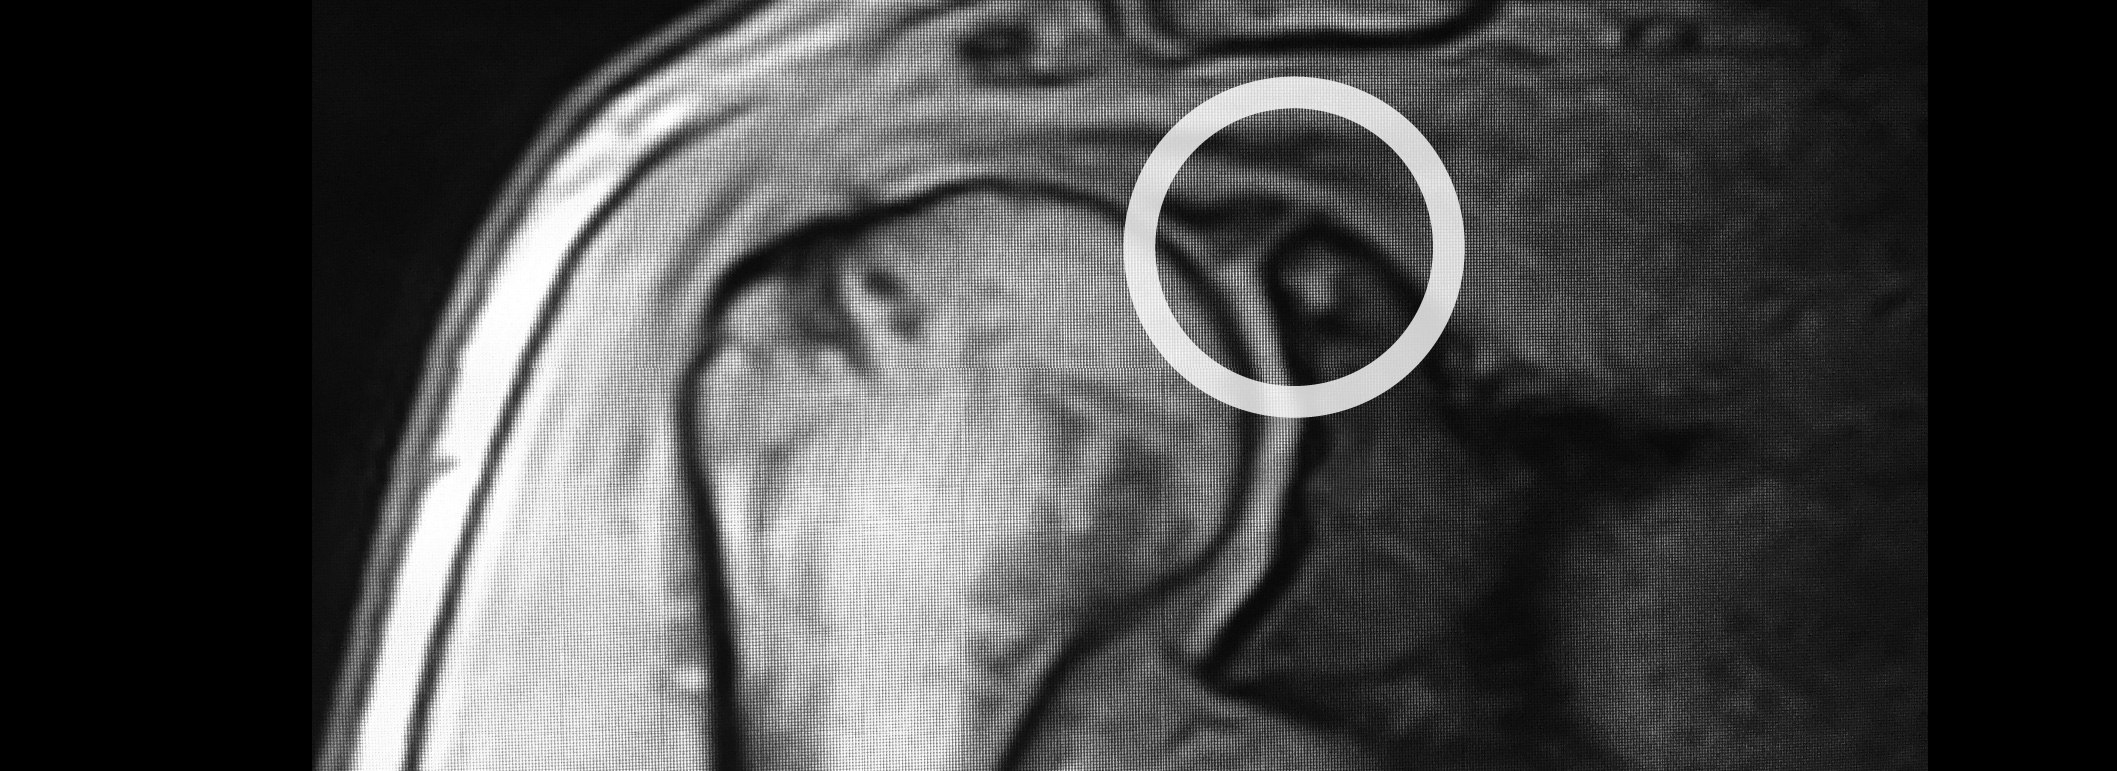

En general, el ortopedista es el especialista para diagnosticar una lesión en el labrum del hombro, realizando un examen físico detallado de la articulación y, para confirmar su diagnóstico de rotura del labrum superior hombro, puede recomendarse una resonancia magnética para visualizar la lesión.

La artrografía por resonancia magnética es la prueba diagnóstica más utilizada ya que se usa un contraste en la articulación para detectar la lesión y el lugar donde se encuentra.

En muchas ocasiones, los síntomas del paciente son confusos porque además hay lesiones asociadas del manguito rotador, laxitud capsular, condromalacia glenohumeral, entre otras, por lo que la artrografía por resonancia magnética o la artroscopia son las pruebas diagnósticas más recomendadas.